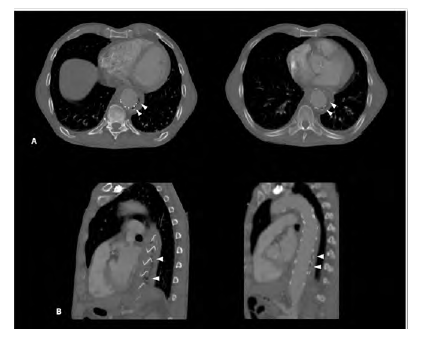

A 62-year-old man, heavy smoker, presented at the emergency department with dysphagia lasting for one month. Based on computed tomography (CT) he was diagnosed with a saccular descending aortic aneurysm and was electively submitted to TEVAR, promptly resolving his clinical complaints, and discharged. One-month after the endovascular procedure, again in an emergency setting, he returns to our centre complaining about chest pain and haematemesis. At presentation, the patient was hemodynamically stable. The CT scan showed ectopic gas inside the aneurysmatic sac (Figure 1) and dilation of the TEVAR landing zones leading to a deficient apposition of the stent graft proximally and distally. He then underwent an oesophagogastroscopy in which a segment of the stent graft was visualized. No hemorrhagic foci were identified in both exams.

Figure 1 CT angiography of the descending thoracic aorta showing the TEVAR stent graft surrounded by air (arrowheads) in an axial (A) and sagittal (B) planes.